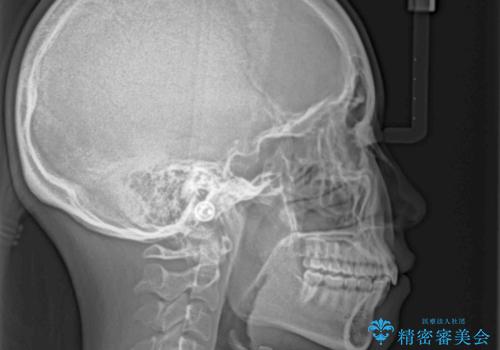

- 上の前歯の出っ歯と前歯の深い咬み合わせを治したいとのことで来院された患者様です。

上顎の歯は後方移動とIPR(歯と歯の間を削る)によって口元が引っ込むように、下顎は歯列全体の拡大とIPRによって上顎とバランスよく咬み合うように設計し、インビザラインにより治療を行うこととしました。

上顎歯列の後方への移動量が多く、右側の奥歯の咬み合わせを改善する必要もあったため、治療には長期間を要しました。